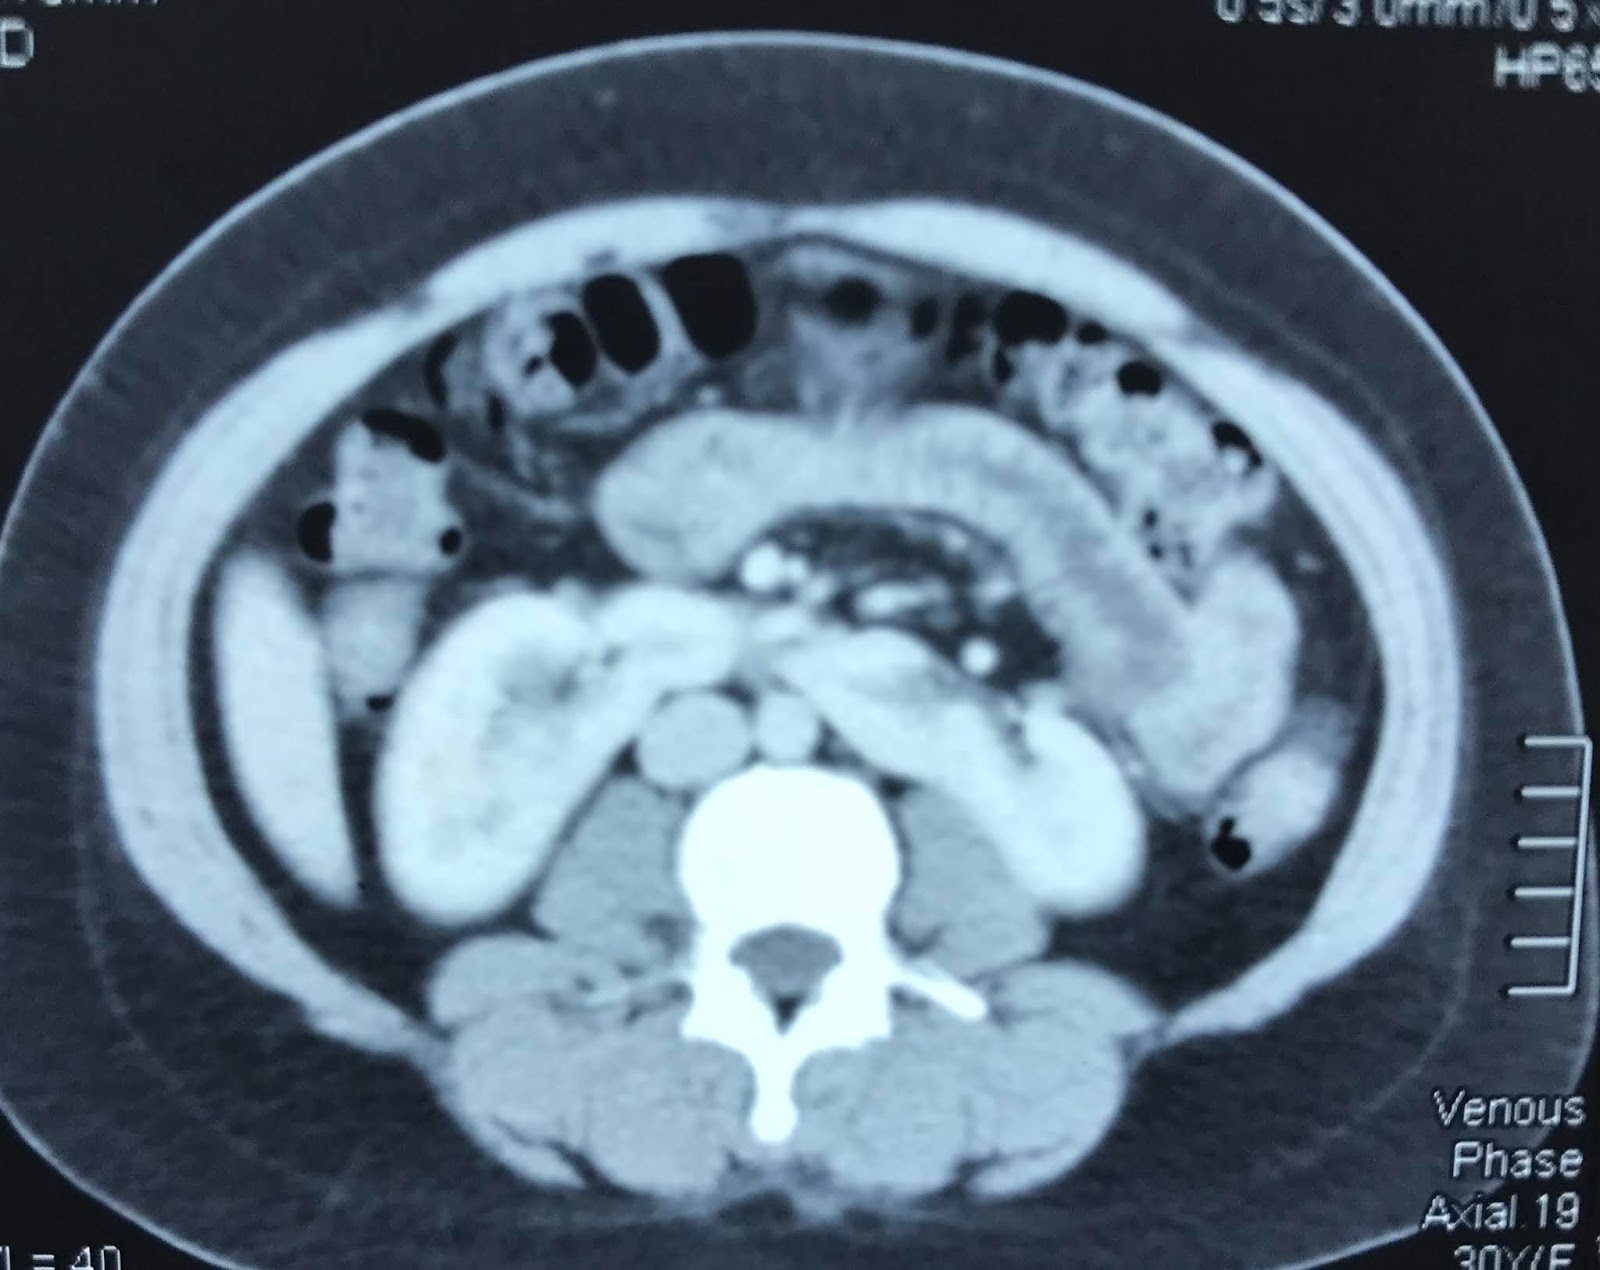

VIETNAMESE MEDIC ULTRASOUND CASE 560 TUMOR IN HORSESHOE KIDNEY, Dr Horseshoe Kidney Tumor We undertook this study to discuss various anomalies associated. horseshoe kidney (hsk) is a common renal fusion anomaly. surgical management of horseshoe kidney tumors is complex, but feasible through both open and minimally invasive surgery after meticulous. — horseshoe kidney is a rare condition where the kidneys fuse together at their base, forming a u or horseshoe.. Horseshoe Kidney Tumor.

VIETNAMESE MEDIC ULTRASOUND CASE 560 TUMOR IN HORSESHOE KIDNEY, Dr Horseshoe Kidney Tumor — rcc is the most common neoplasm associated with horseshoe kidney. We undertook this study to discuss various anomalies associated. horseshoe kidney (hsk) is a common renal fusion anomaly. — patients with horseshoe kidneys are at increased risk for upj obstructions, nephrolithiasis, vesicoureteral reflux, urinary tract infections,. — horseshoe kidney is a rare condition where the. Horseshoe Kidney Tumor.

VIETNAMESE MEDIC ULTRASOUND CASE 560 TUMOR IN HORSESHOE KIDNEY, Dr Horseshoe Kidney Tumor The tumor can localized at any part of the. surgical management of horseshoe kidney tumors is complex, but feasible through both open and minimally invasive surgery after meticulous. horseshoe kidney (hsk) is a common renal fusion anomaly. — rcc is the most common neoplasm associated with horseshoe kidney. — horseshoe kidney is a rare condition where. Horseshoe Kidney Tumor.